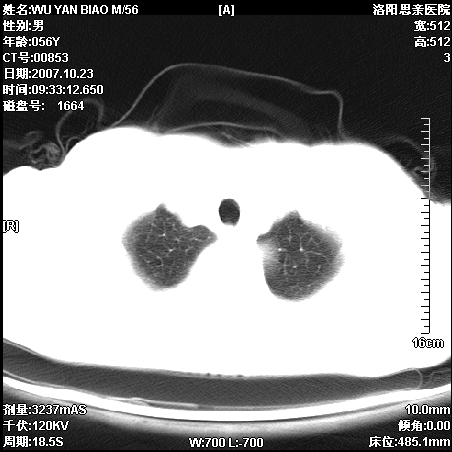

标题: CT10160:M56Y,体检发现,病人无不适,病人随访中 [打印本页]

标题: CT10160:M56Y,体检发现,病人无不适,病人随访中

后上纵隔占位,与肺交界清,宽基底附着脊柱,密度均匀,局部骨质无明确改变.

考虑;神经源性肿瘤,---起源交感n链?,不除外肠源性囊肿.

与纵隔关系密切,密度均匀。只能考虑:后纵隔神经原性肿瘤!

1、病灶在后纵隔脊柱旁沟内,此处是神经原性肿瘤的好发部位

2、病灶边缘光滑整齐,更说明病灶来于纵隔,由于有胸膜的包裹所以才导致这么光滑的边缘

3、病灶内的密度均匀